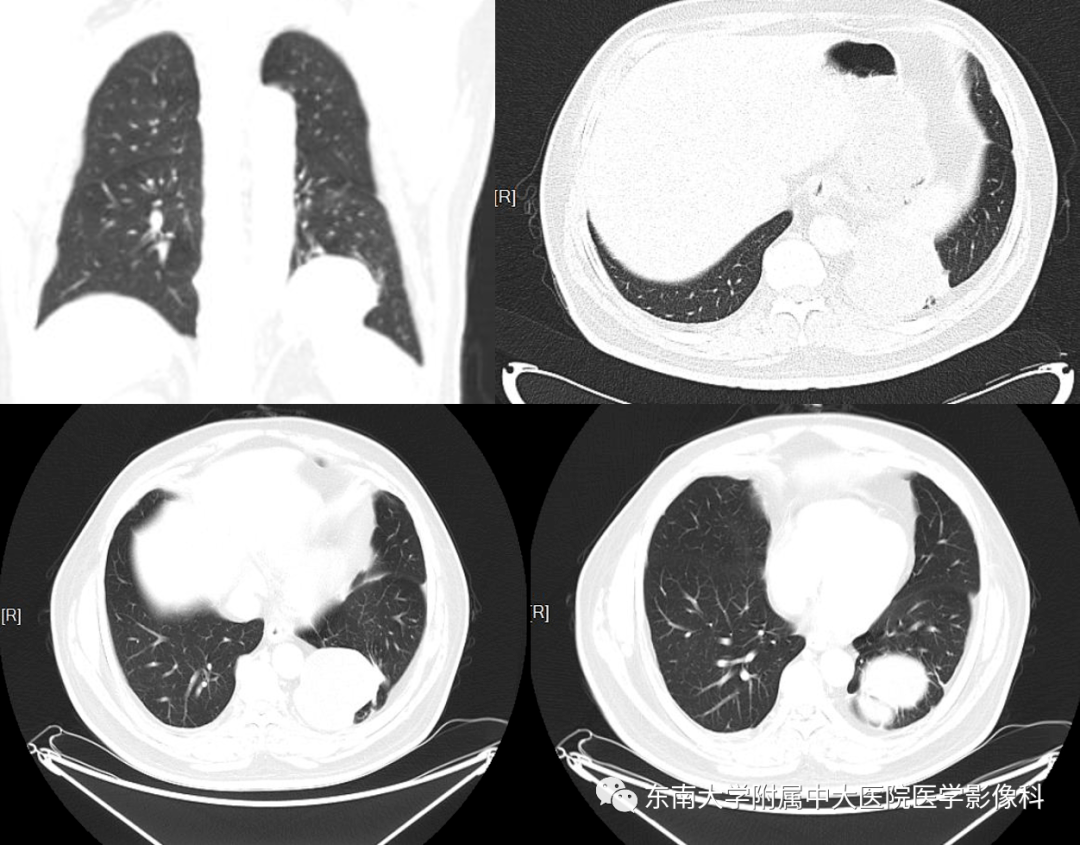

【影像读片】肺隔离症?